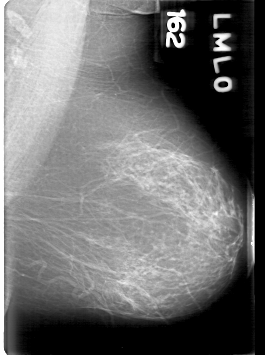

D_4094_1.LEFT_MLO

LEFT_MLO LINES 5311 PIXELS_PER_LINE 3961 BITS_PER_PIXEL 12 RESOLUTION 43.5 NON_OVERLAY

FILE: D_4094_1.RIGHT_MLO.OVERLAY

TOTAL_ABNORMALITIES 1

ABNORMALITY 1

LESION_TYPE MASS SHAPE ROUND MARGINS OBSCURED

ASSESSMENT 0

SUBTLETY 4

PATHOLOGY BENIGN

TOTAL_OUTLINES 1

BOUNDARY